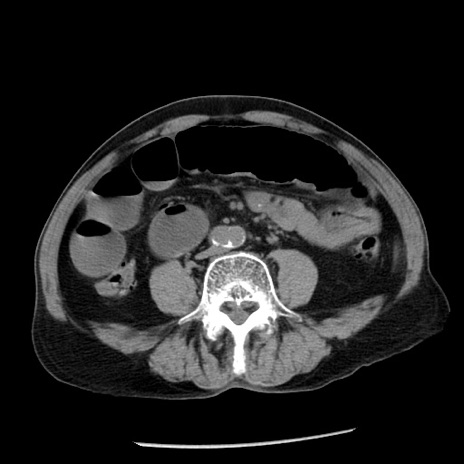

症例26(横断像)

【症例】80歳代男性

【主訴】嘔吐

【現病歴】昨晩2回嘔吐あり、今朝になっても嘔吐あり。来院。

【既往歴】胃潰瘍

【身体所見】意識清明、BT 37.6℃、BP 166/95mmHg、HR 100bpm、SpO2 97%、腹部:平坦・軟、腸蠕動音聴取良好、圧痛なし。

【データ】WBC 21900、CRP 1.46